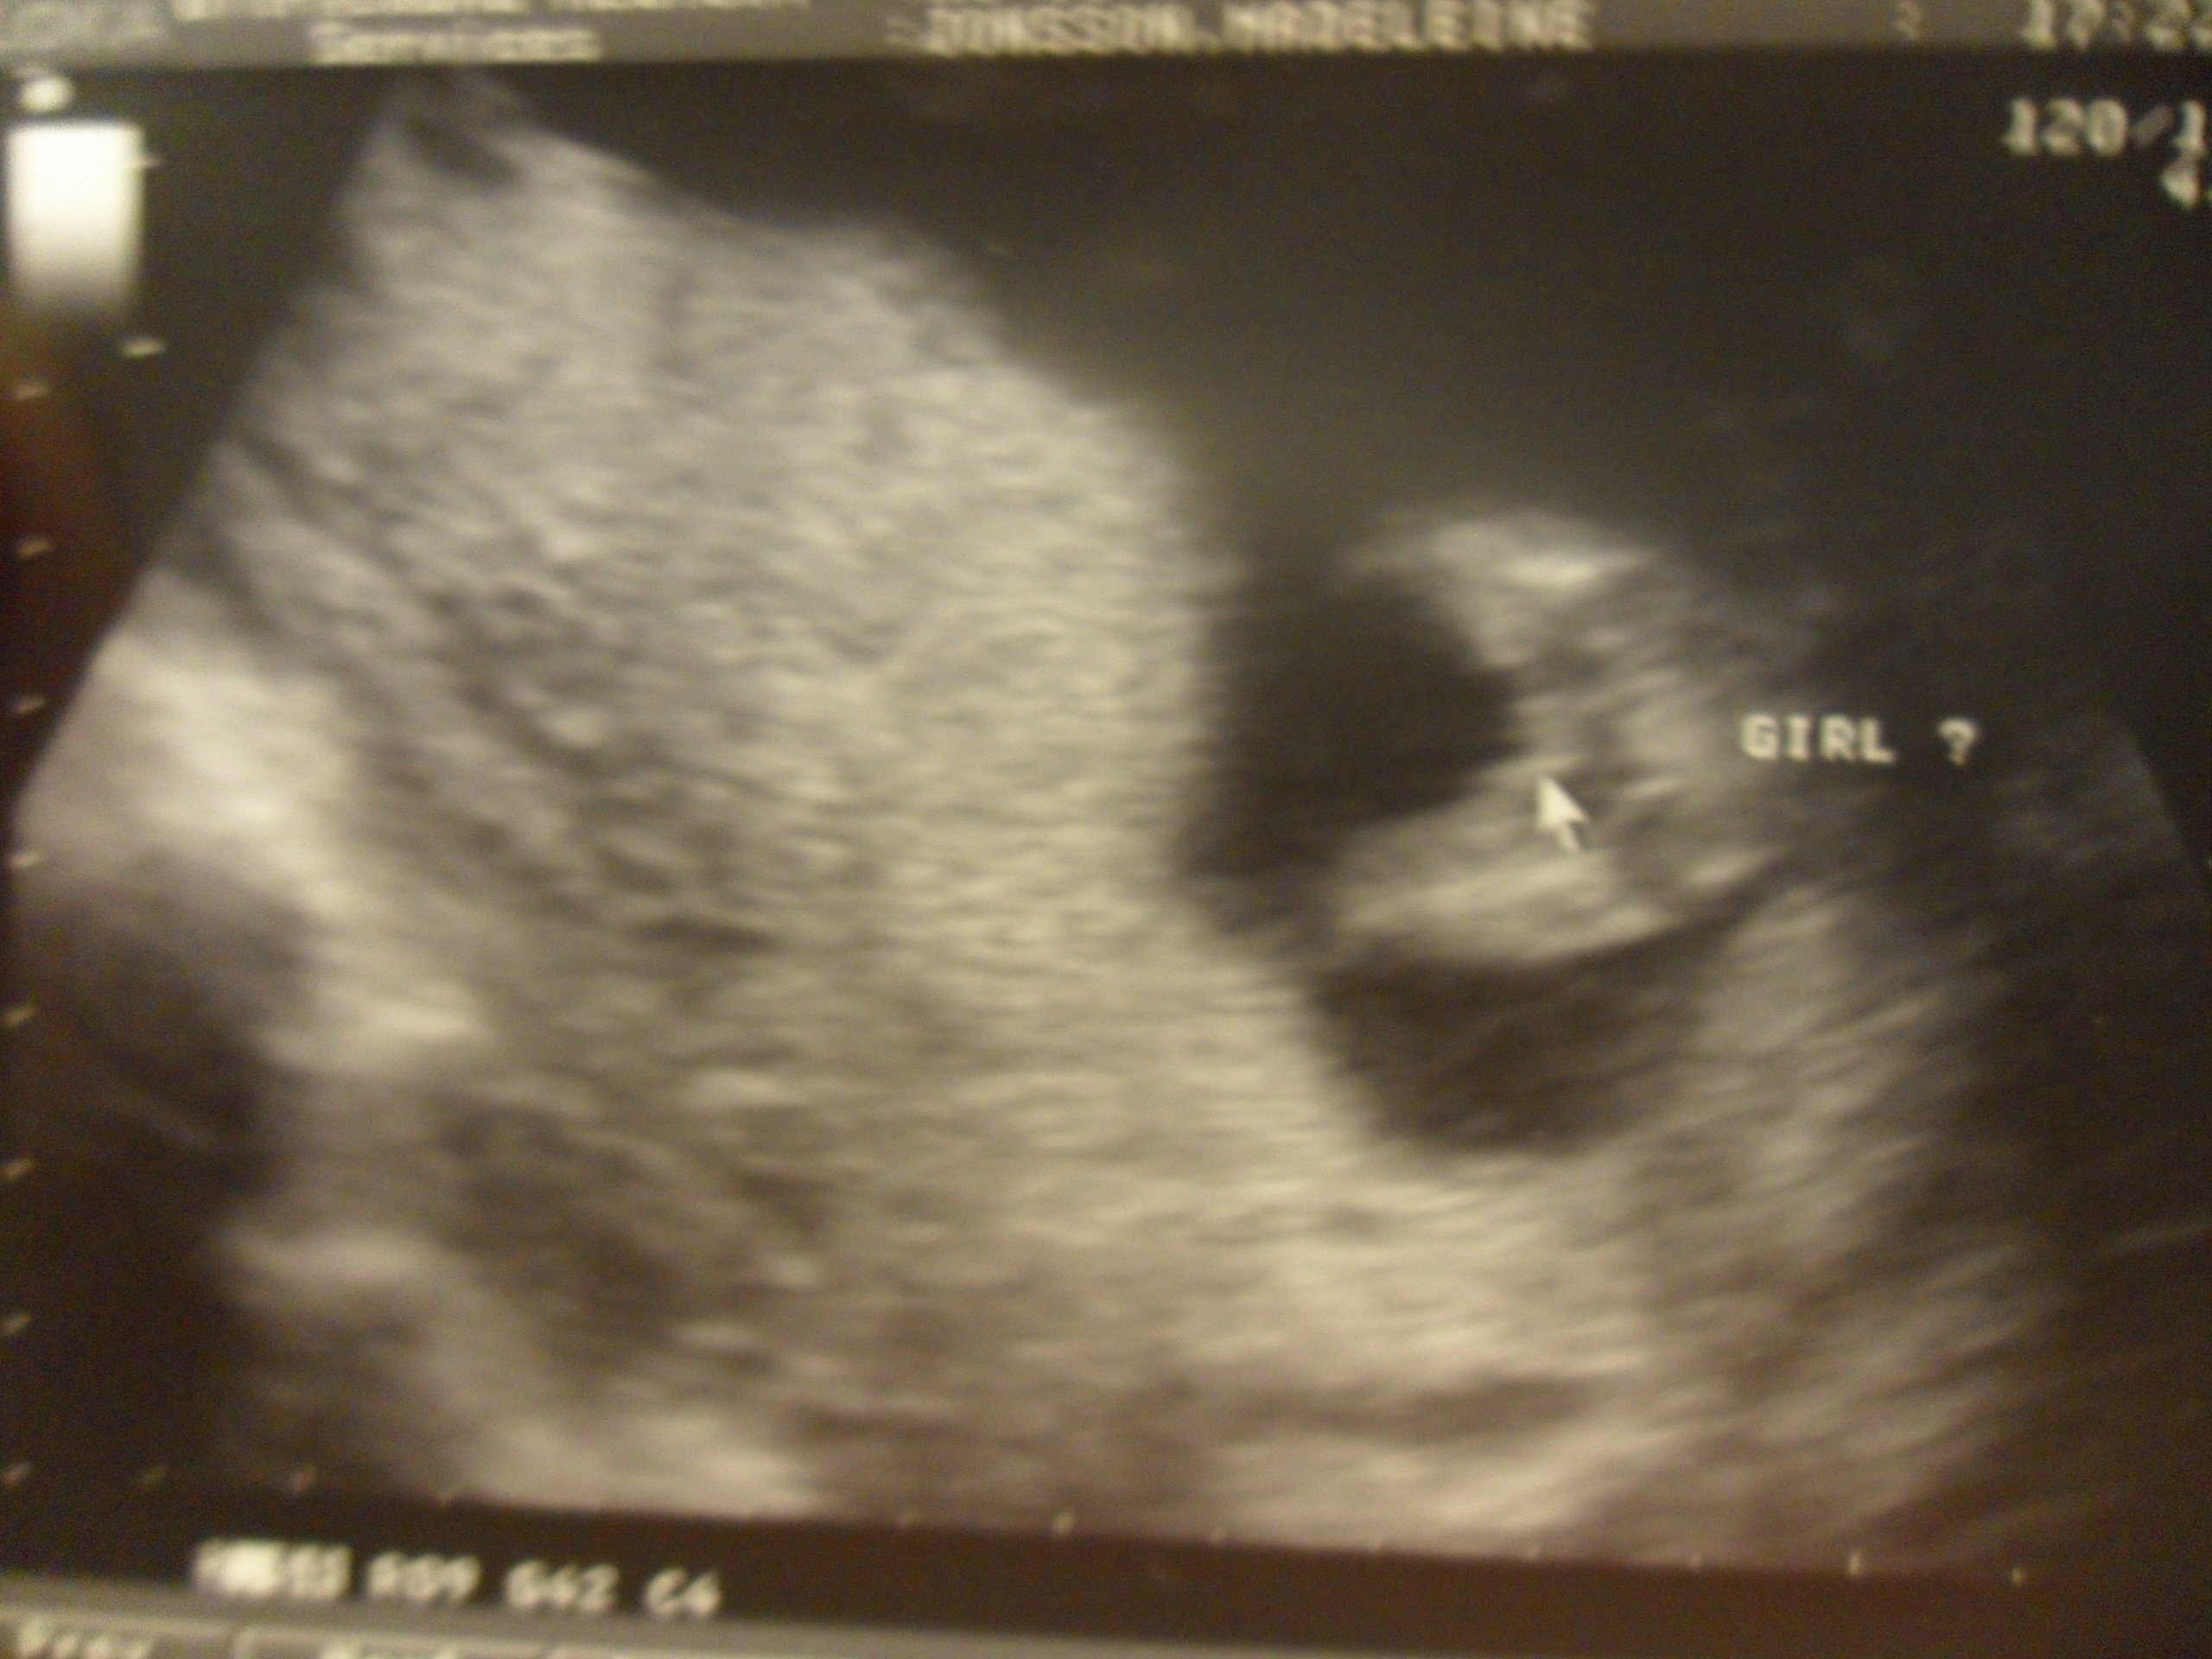

navelsträngen mellan bena och de va svårt att se.. Jag fick hosta och

lägg mig på sidan för att få strängen att flytta sig. Tillslut så kunde vi

se en klar bild av hela härligheten haha.. 3 vita linjer, vilket betyder TJEJ.

en profilbild. Iaf så dubbel och trippel kollade tekniker-tjejen flera

ggr och hon frös till lite en stund när bönan hade handen mellan benen

och man såg 2 fingrar och hon va rädd att de kanske va en snopp iaf.

Och efter det dubbelkollade hon några fler ggr för att va säker. Så..

efter 20min så hade vi sett lilla snippan säkert 10ggr och vi är rätt säkra

på att det stämmer att vi ska få en liten tjej 🙂

Och tjej-delarna igen. Här ser ni att man ser alltihoppa ‘underifrån’ liksom.